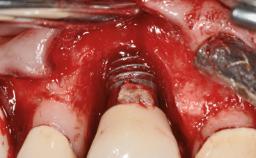

A 77-year-old male patient was referred for the management of frequent and repeated acrylic fracture of his existing mandibular fixed full-arch implant-supported metal/acrylic prosthesis. He also complained about softtissue soreness and the lack of retention and stability of his maxillary removable partial metal/acrylic prosthesis. Both prostheses had been delivered two years previously as part of his full-mouth rehabilitation (caries, tooth wear, tooth fracture). His medical history revealed high blood pressure, controlled with the use of antihypertensive medication.

# of Implants 5

Type of Implants Two-Piece

Defining Characteristics Fully edentulous lower jaw to be rehabilitated with two or more implants

Modality > 4 implants, extending to mental nerve region

Bone Volume Horizontally and vertically sufficient